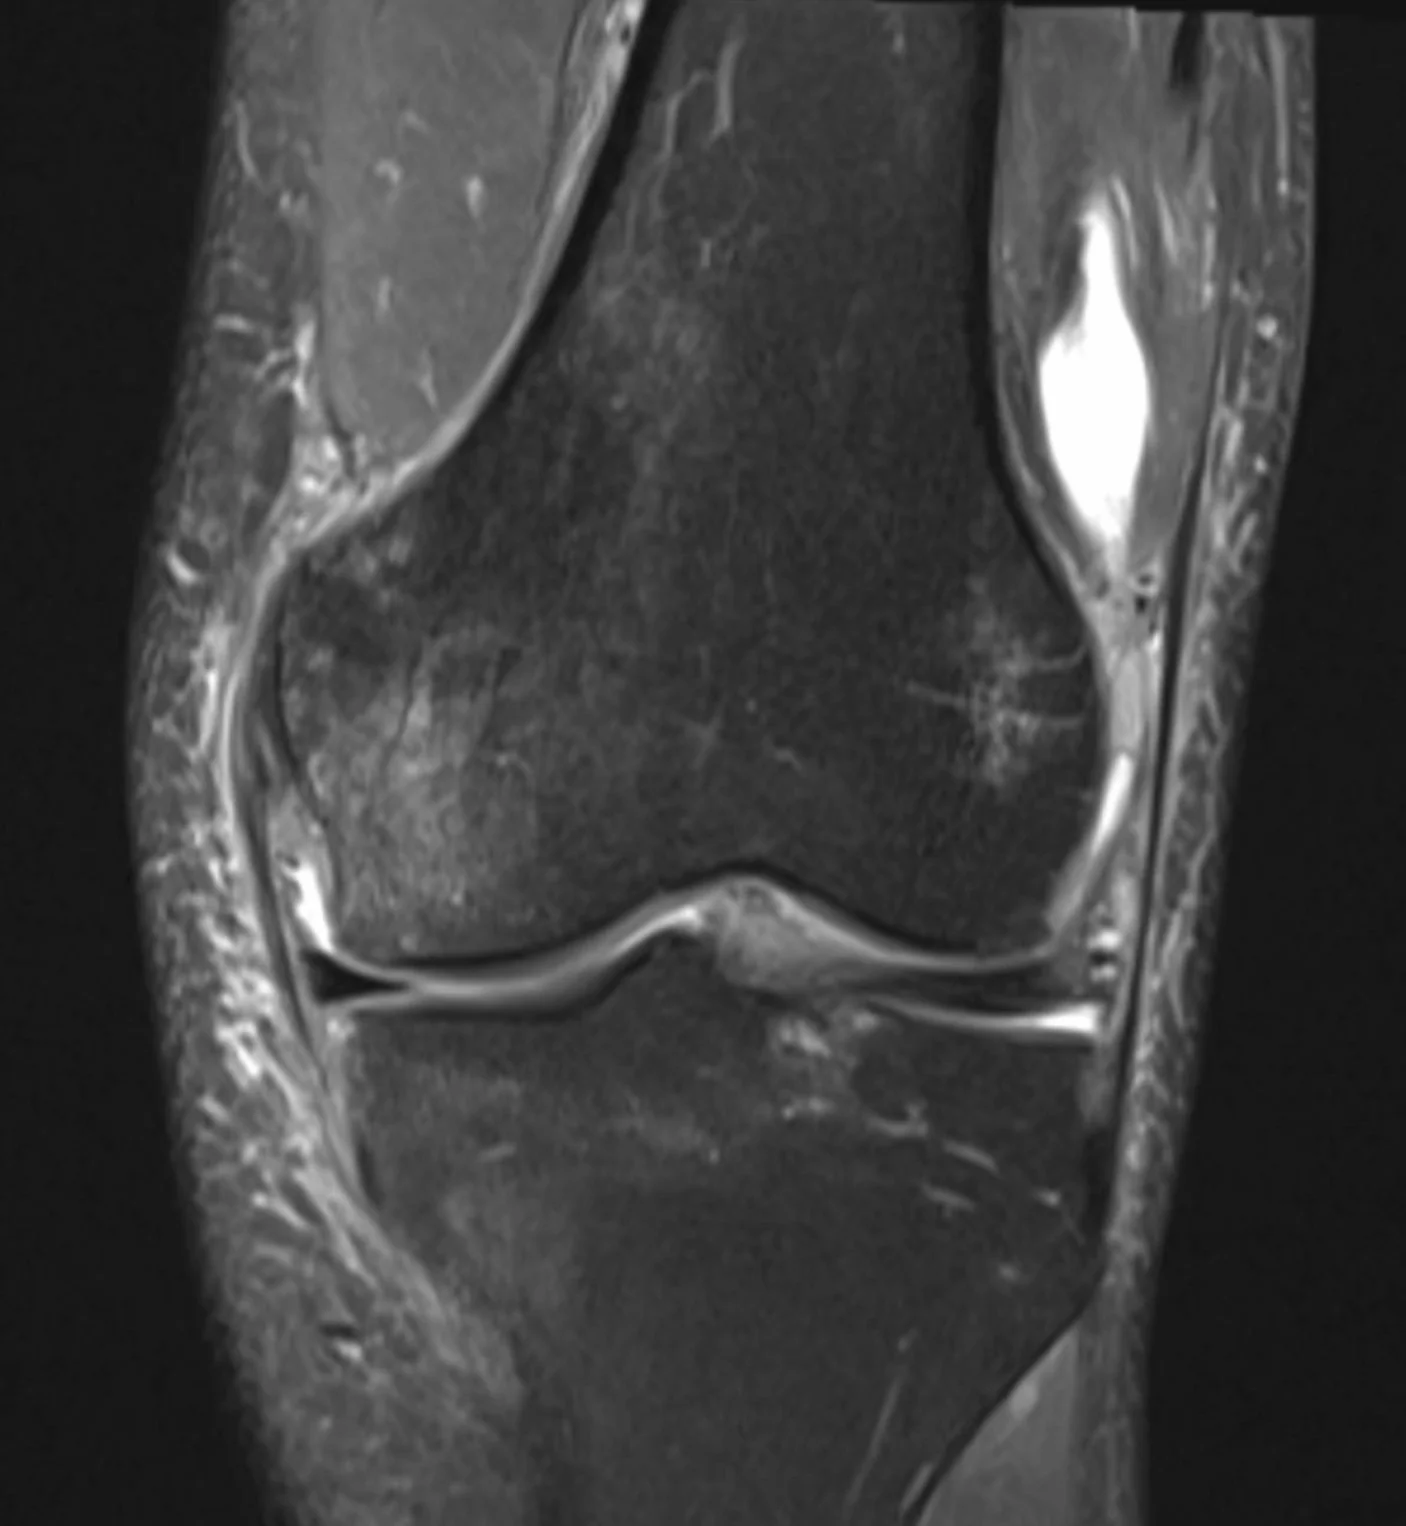

I have my surgery date for the stitching up of my meniscus. February 3rd. This gives me a little over 5 weeks to get myself in shape for it. It’s been a rough ride trying to maintain fitness with chronic pain. Certainly for the first 3-4 months, but recently there has been less pain. So I am able to cycle indoors and even do non-load bearing weights (seated bench stuff). My intention is to be in as good shape as possible going into the surgery. The idea being that the rehab will be easier if I have a level of strength and fitness going in.